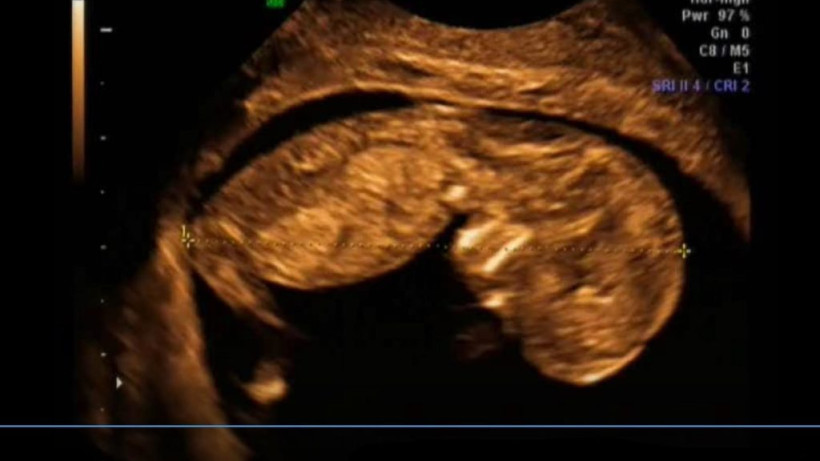

W 12. tygodniu życia Twoje dziecko ćwiczy wytrwale jak sportowiec. Ale potrafi też płakać!

Maleństwo mierzy 7,5 cm długości i waży 14 g. Jest wielkości średniego jabłka.